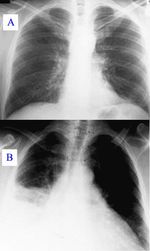

질병이 진행되면서 일부 환자에게서는 비정형 폐렴으로 발전할 수 있으며, 이는 감염 후 첫 4~5일 동안 생명을 위협하는 급성 호흡 부전 증후군(ARDS)을 유발할 수도 있다.[7] 드물게는 (육아종성) 간염이 발생하기도 하는데, 증상이 없거나 불쾌감, 발열, 간 비대, 복부 우상부 통증 등이 나타날 수 있다. 간염 발생 시 트란스아미나제 수치 상승은 흔하지만 황달은 드물다.[8] 또한 매우 드물게 망막 혈관염이 발생할 수도 있다.[8] 전체 급성 큐열 환자의 약 20% 정도에서 폐렴이나 간염 증상을 보이는 것으로 알려져 있다.